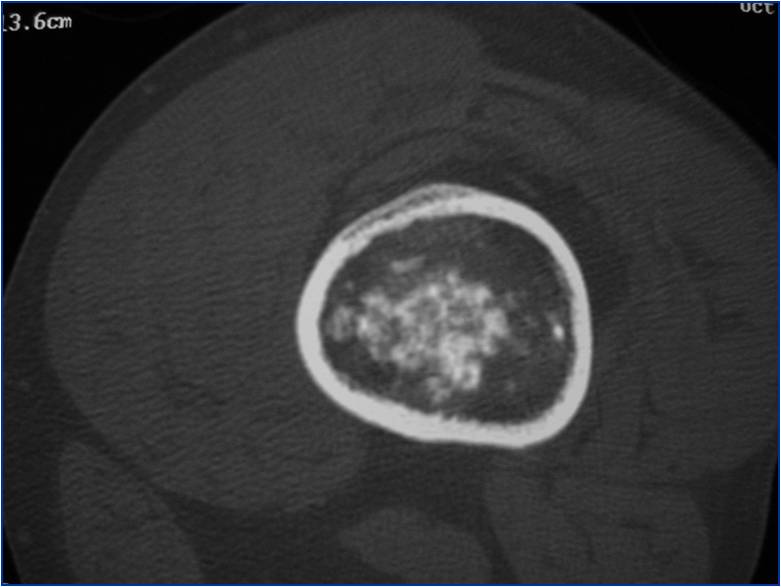

- Localized, radiolucent defect usually with punctate calcifications

- Calcifications are typical but not always present

- Matrix may demonstrate various degrees of calcification

- Calcifications are stippled, punctate, popcorn like calcifications and “Ring and Arc” calcifications

- Chondroid matrix with calcifications in majority of tumors

- Approximately 20% have limited or no calcifications